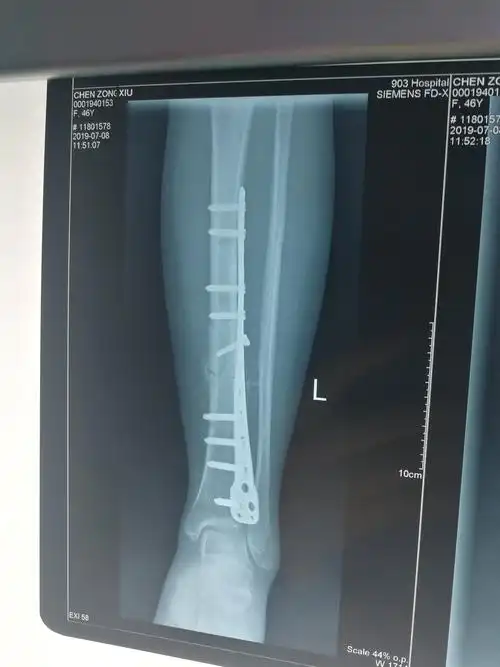

经过2个月的治疗后复查片可见骨折端对位对线良好,已有骨痂生成.

术后2月骨痂生长良好

术后6个月见少量骨痂

见左胫骨骨折端为纤维组织填充,无连续性骨痂,无明显的炎性渗出物

经过1个月的治疗后复查片可见骨折端对位对线良好,可见大量骨痂生长.

术后一月复查,骨痂生长良好